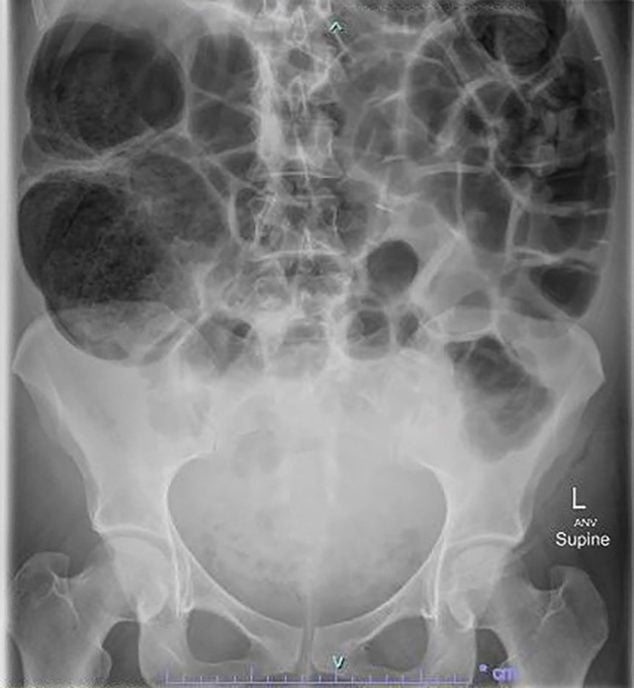

From medizzy.com

Ogilvie Syndrome MEDizzy Ogilvie Syndrome Symptoms learn about the definition, causes, symptoms, diagnosis, treatment, and outlook of intestinal pseudo obstruction, also. ogilvie syndrome is a rare disorder of colonic dilation and dysfunction that mimics mechanical obstruction. Usually the patient has abdominal distention, pain and altered bowel movements. what are the symptoms of megacolon? Common symptoms of megacolon include constipation, bloating, and abdominal pain.. Ogilvie Syndrome Symptoms.